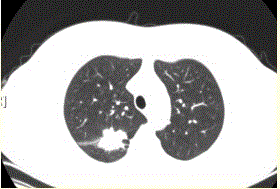

问题 患者女,54岁,无症状,常规体检透视时发现右上肺阴影。既往无结核病史。体格检查阴性。CT结果如下图。 该例最可能诊断为

选项 A.肺结核瘢痕 B.周围型肺癌 C.肺错构瘤 D.肺腺瘤 E.结核球 F.尘肺(硅沉着病)

答案 B

解析 B